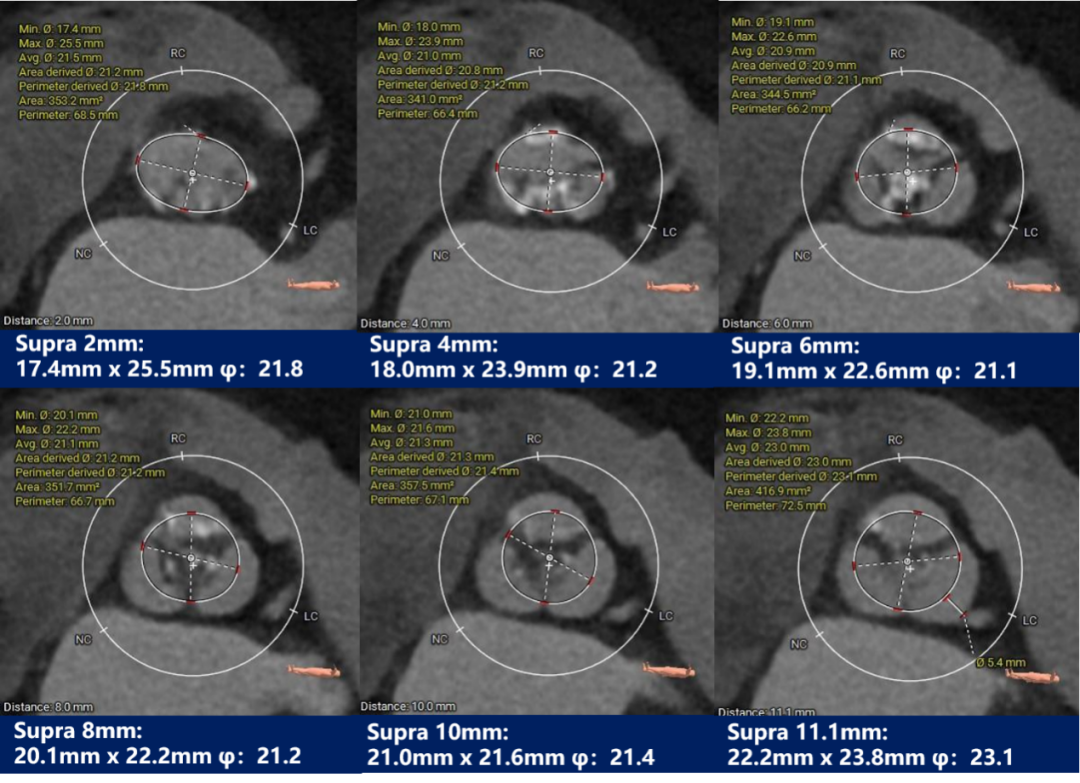

瓣上测量

瓣上测量:窦部发育均匀,瓣叶中重度钙化并明显增生肥厚,钙化分布相对均匀,主要分布在瓣叶边缘及管壁附着缘,左无窦间有部分钙化粘连。